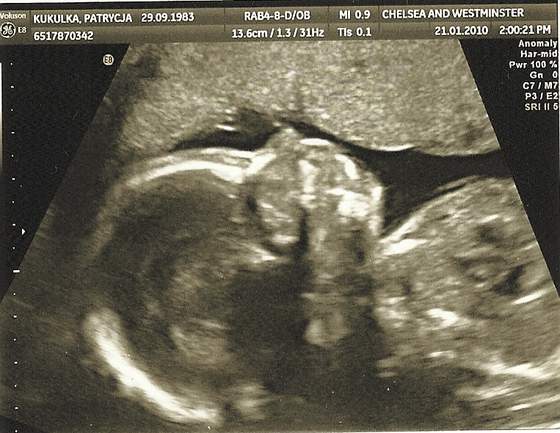

ja tez pochwale sie moim synkiem

jest podobny do swojego starszego brata

malenki Max lub Anthony:-)